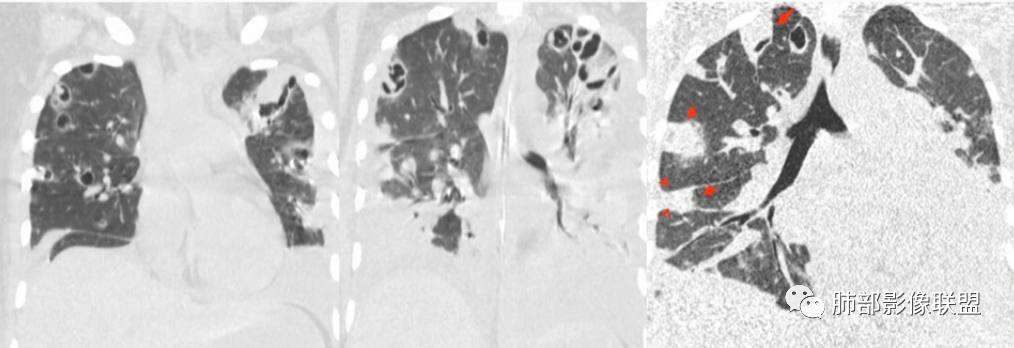

2.影像上肺多发混合密度片影,随机分布,胸膜下分布优势,病灶边界大多隐约可辨,偏柔和,动脉血管影穿行,未见钙化、液化空洞、或明确气囊影,未见树芽征。

3.影像方面:双肺多发病灶,随机分布,且有相当部分沿胸膜下,是可以符合血流感染的。

一、影像特点

1.外围分布,胸膜下为主,两肺弥漫结节或胸膜下楔形影,边界清,周围伴有GGO

2.反晕征:往往紧贴胸膜,并且胸膜侧无环,周围GGO

3.空洞:分为两类。

第一类,偏心空洞,一侧壁厚,周围实变明显。

第二类,薄壁空洞(偏中后期):壁薄且均匀,内外壁光滑,张力高,内有气液平面、间隔影,各空洞相对独立互不相通

4.囊:张力高,壁薄,内外壁光滑,可有间隔

5.边缘收缩明显,结节密实,边缘收缩、凹陷,周围长索条影,提示吸收好转

6.胸腔积液、脓胸